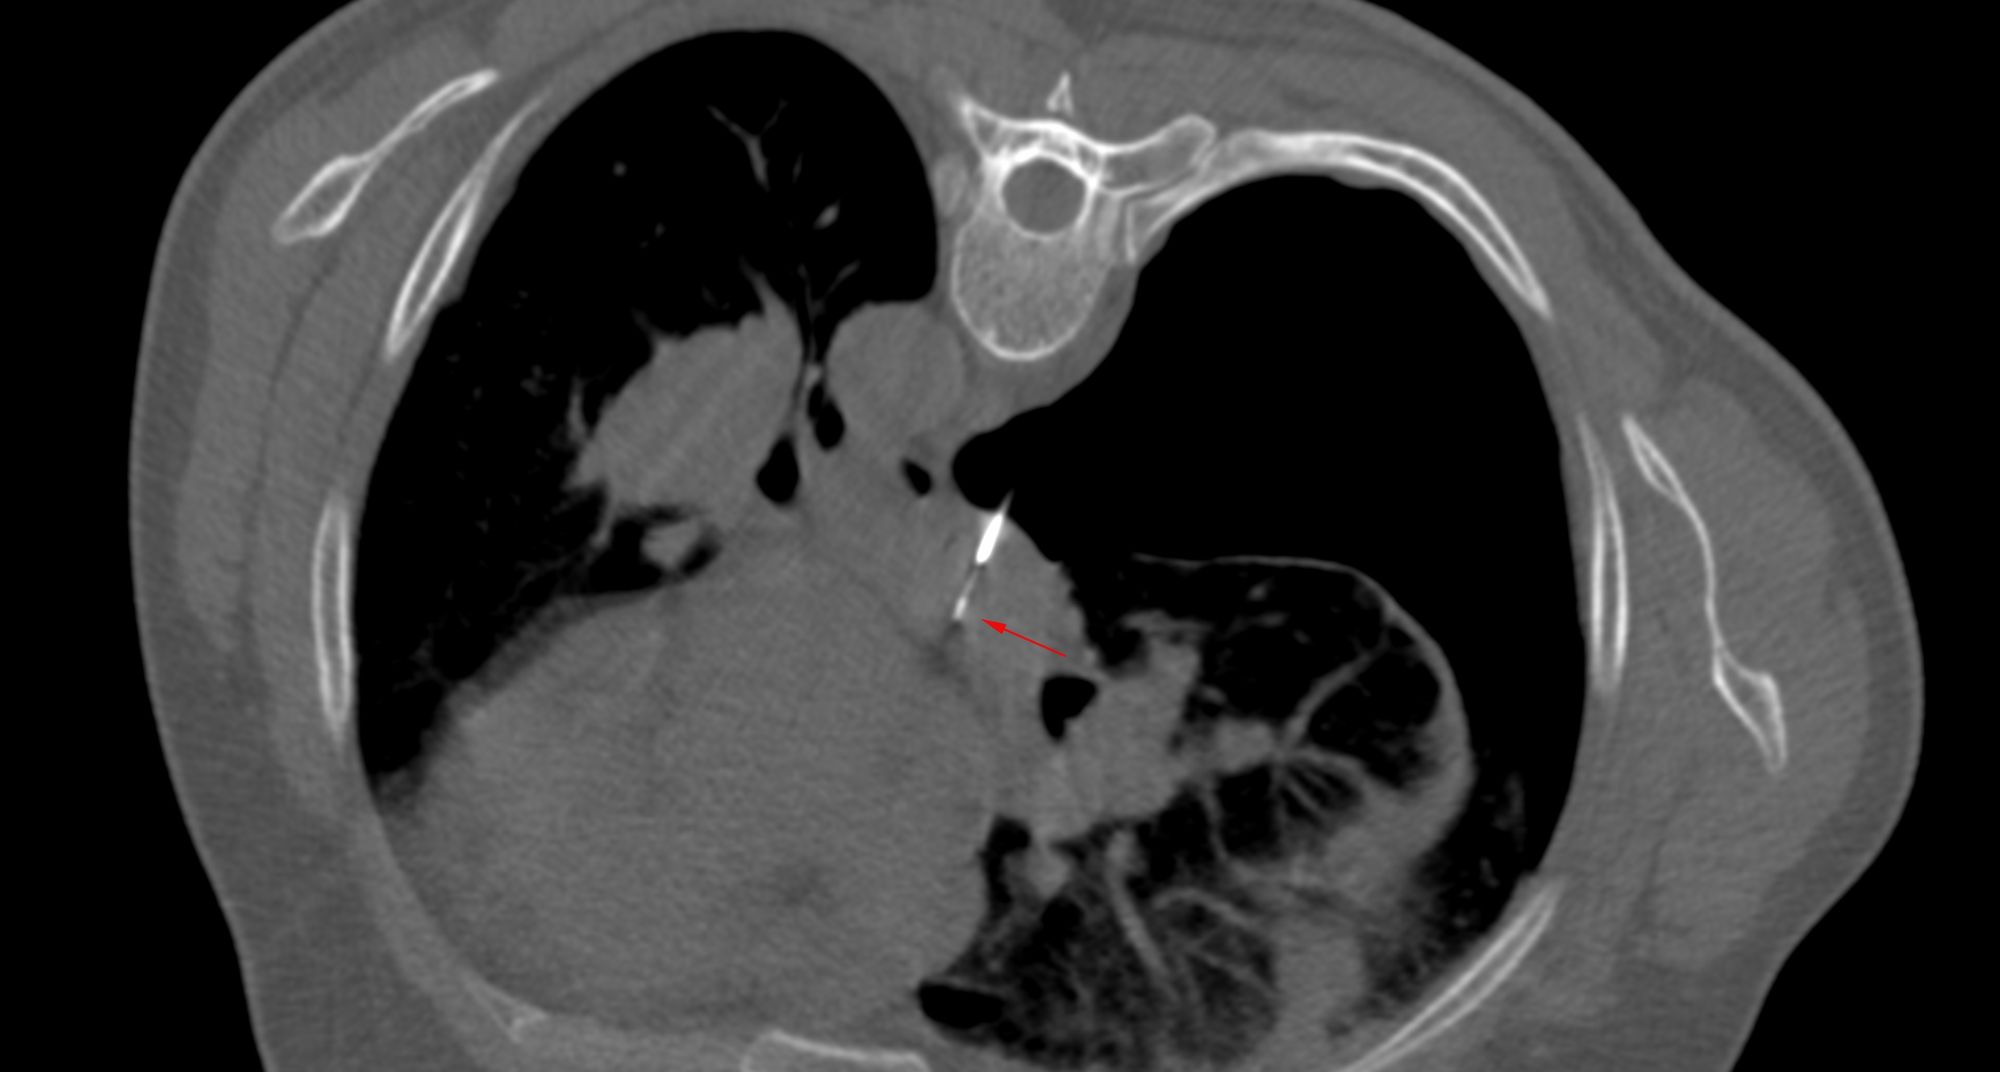

Case 31: Subcarinal Node Biopsy - Transpulmonary Approach